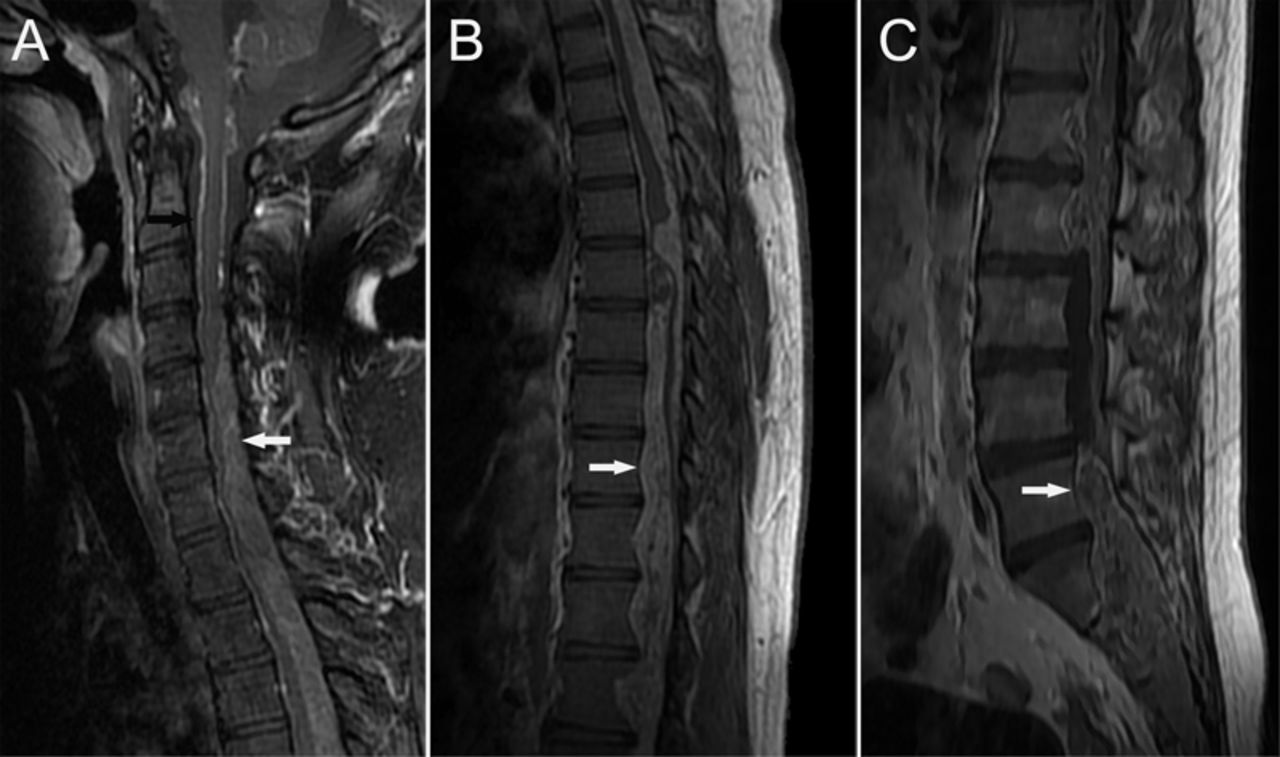

图1

脊髓室管膜瘤图像

脊柱矢状t1加权磁共振成像(a - c)演示了一个类似硬膜内的质量不均匀增强信号,从C4水平延伸至远端脊柱(白色箭头)。未发现病变仅在C1级别C3水平(A,黑色箭头)。